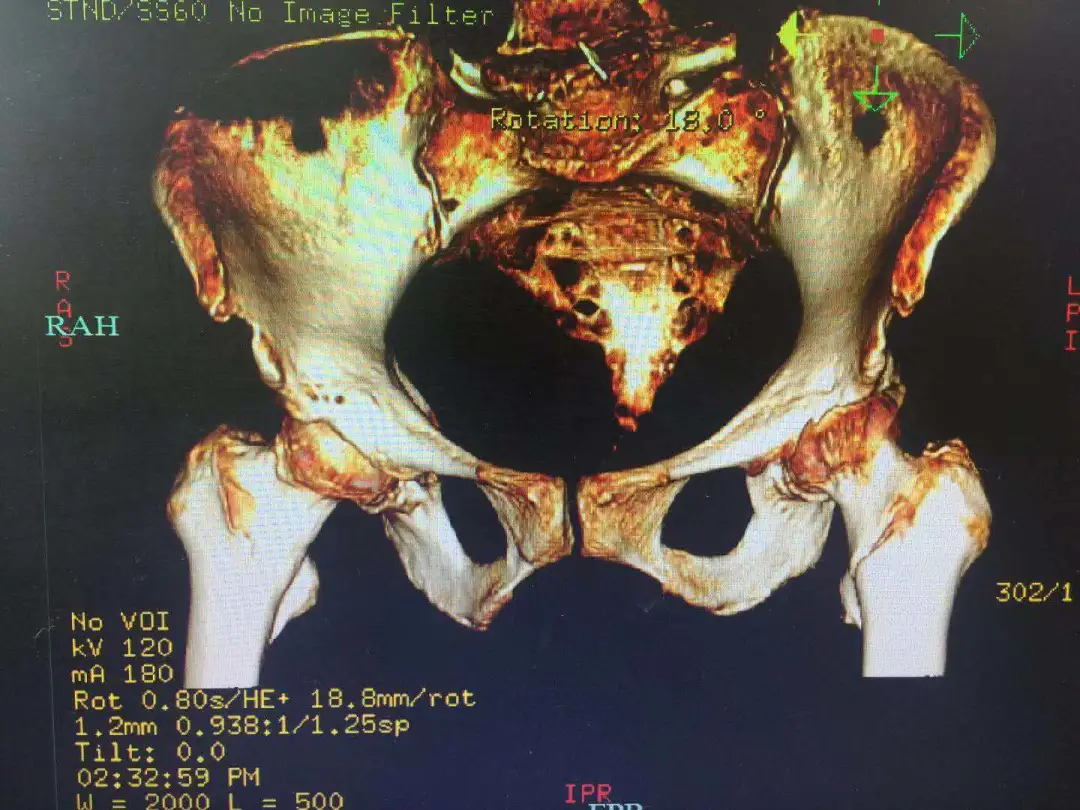

87 岁宋奶奶术前影像学资料

上海海华医院放射科及时准确的出片为临床诊断提供有力支持